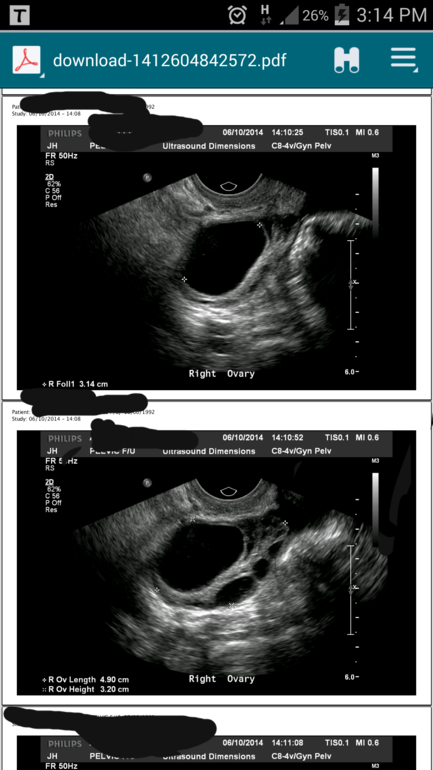

Вообщем надумала сходить на узи чисто от любопытства...и что меня там ожидалооо....Мой Дф 1.85см вырос до 3.14см ((((неужели киста? ?!!!

Или это киста желтого тела?! Фото снизу скину...может кто понимает и скажет мне что это....

Вот еще фото...

Яичник в другом ракурсе